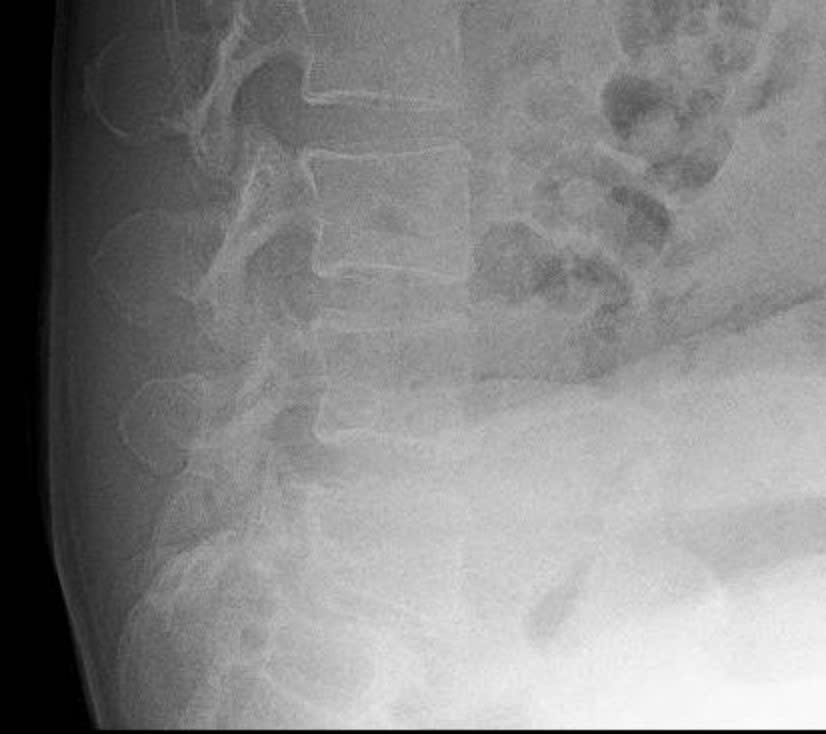

2.3. Điều trị bệnh lý cột sống: với sự hỗ trợ chuyên môn của Bệnh viện Chợ Rẫy, Bệnh viện Nhân Dân 115 TpHCM, Khoa đã và đang thực hiện phẫu thuật các trường hợp bệnh lý cột sống thắt lưng như: gãy cột sống; lấy nhân đệm thoát vị đơn thuần, qua kính vi phẫu; phẫu thuật trượt đốt sống; bơm xi-măng điều trị xẹp đốt sống do loãng xương;…Điều trị nội ngoại khoa các trường hợp Viêm thân sống đĩa đệm.

Phẫu thuật cột sống với sự hỗ trợ chuyên môn tuyến trên

Trước mổ

Sau mổ

Phẫu thuật Trượt đốt sống L5S1